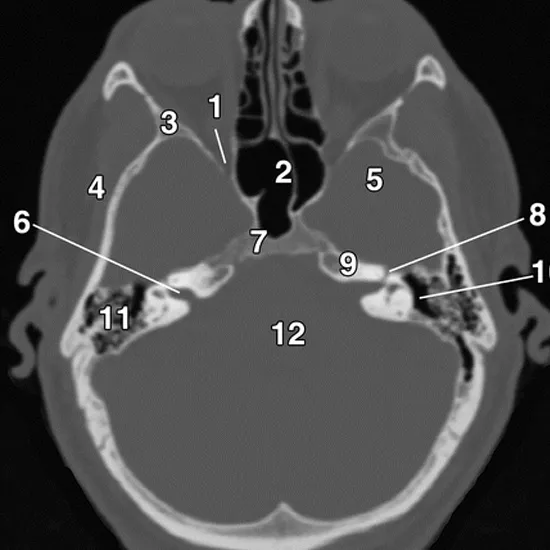

Contrast Enhanced Computed Tomography / CECT of the base of the skull is a diagnostic imaging procedure to detect the issues in the base of the skull such as fractures, CSF leakage, lesions etc.

CECT base of the skull is an imaging modality that is used to detect the lesion and characterization and to diffentiate between organs more preciously.

The CT brain with contrast is recommended to look at the structures of the brain and to evaluate for the presence of pathology like –